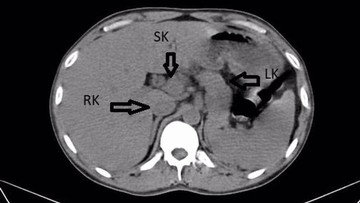

Penemuan organ ginjal ketiga yang berbentuk tidak biasa ini menjadi fokus utama setelah infeksi berhasil ditangani. Bentuk organ tambahan tersebut dideskripsikan memiliki morfologi yang menyerupai tapal kuda.

Dilansir dari laporan kasus tersebut, keberadaan organ tambahan ini menambah kompleksitas diagnosis awal yang hanya berfokus pada penanganan infeksi akut yang dialami pasien. Studi lebih lanjut mengenai ginjal ektopik ini sangat penting dilakukan.